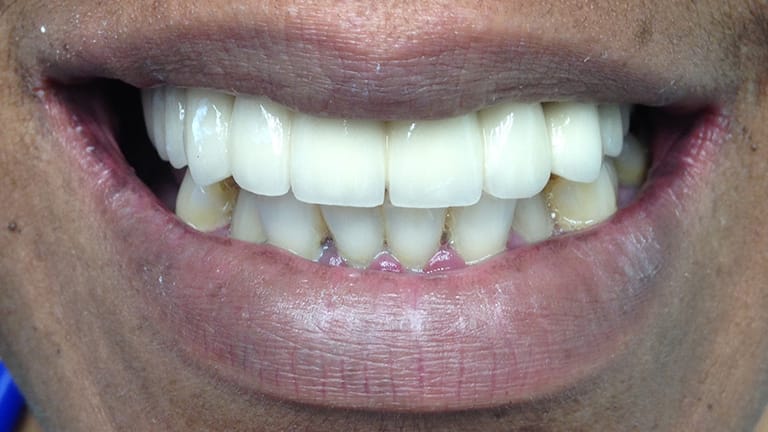

Below is a few examples of what DENTAL IMPLANTS can do for you and your smile!